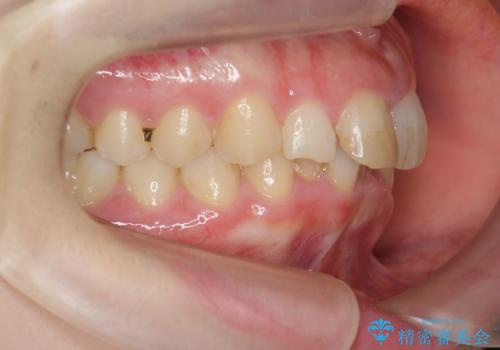

前歯のがたつき 深い噛み合わせを改善したい

- 「前歯のガタつきをきれいにしたい、噛んだ時に下の前歯が見えないことを改善したい」とマウスピース矯正を希望され来院されました。

マウスピースに加え、矯正用マイクロインプラントやゴムを併用し、がたつきや噛み合わせの深さを改善していきます。

ゴムかけやマウスピースの装用時間、しっかりとマウスピースをはめ込むチューウィーをしっかりと使用したことで良好な治療結果を得ることができました。